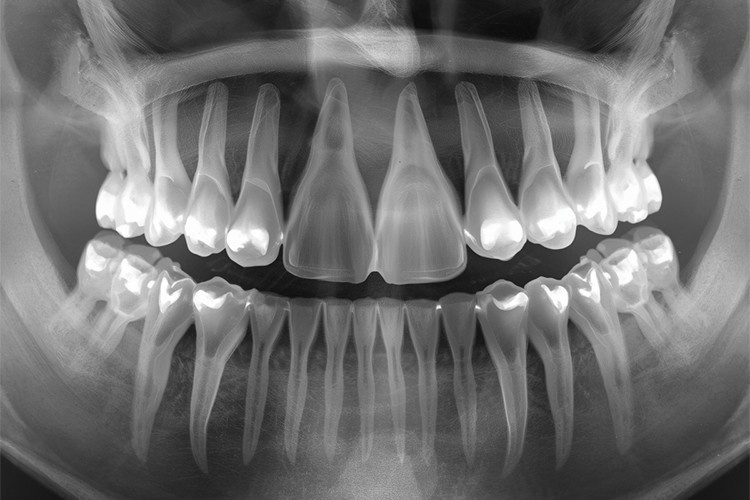

Keep in mind that, in some cases, the eruption of these teeth can pose a risk to neighboring teeth by increasing crowding, contributing to decay, or causing structural damage. If you prefer to prevent future issues, you can remove symptom-free wisdom teeth if X-rays indicate they’re likely to cause problems in the future.